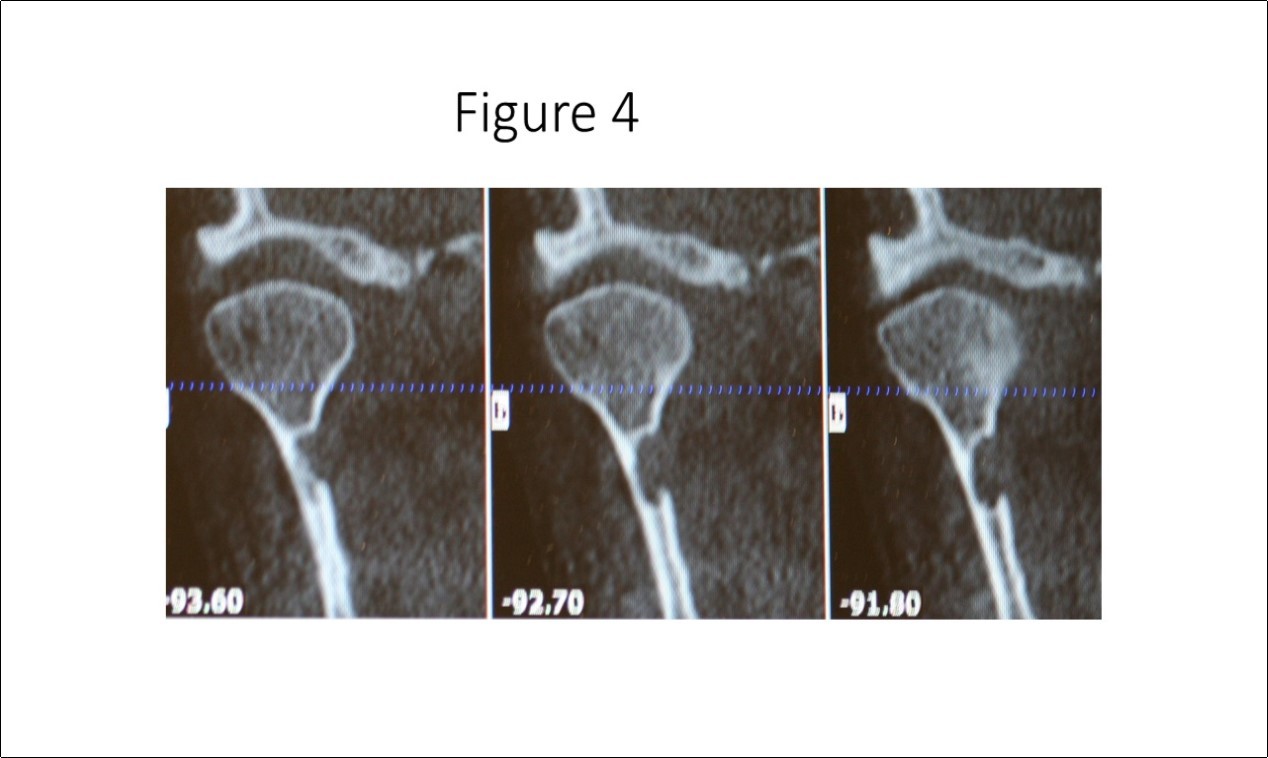

Maxillofacial examination was unremarkable. No facial swelling, masses or asymmetry was observed. The TMJ examination was normal. No pain or tenderness to digital palpation was observed in the right preauricular region. Oral examination of the patient was unremarkable. No trismus was observed as the maximal interincisive opening was greater than 40.0mm. No anterior or posterior open bite was observed. Imagining studies to rule-out intraosseous neoplastic lesions and arrive at a definitive diagnosis consisted of a panoramic radiograph and cone beam CT scan (120 kVp, 5 mA, 7.4 sec). Panoramic radiograph revealed a unilocular, well-circumscribed radiolucency in the right subcondyalar region of the mandible that was close to the posterior border of the condylar neck (Figure 2). Cone beam CT scan (i-CAT FLX, Imaging Sciences, Hatfield, PA) imaging revealed a well-defined unilocular, elliptical shaped radiolucent lesion on the medial surface of the right subcondylar neck of the mandible (Figure 3, Figure 4, Figure 5). The elliptical shaped unilocular lesion involved almost the entire horizontal dimension of the subcondylar neck (Figure 4). Figure 5 shows the three-dimensional CT scan reconstruction (i-CAT FLX, Imaging Sciences, Hatfield, PA) of the medial defect in the subcondylar region of the mandible. Based on knowledge of clinical head and neck anatomy and imaging studies, no treatment was indicated as the diagnosis was consistent with a variant of a Stafne bone cavity of the right subcondylar neck near the parotid gland and not a pathological condition. The patient was informed about the risk of condylar neck fracture due to the critical size of the SBC.

Figure 2.Panoramic radiograph reveals a unilocular radiolucency in the right subcondylar neck of the mandible which is considered a variant of the classic SBC described by Dr. Stafne.

Panoramic radiograph reveals a unilocular radiolucency in the right subcondylar neck of the mandible which is considered a variant of the classic SBC described by Dr. Stafne.